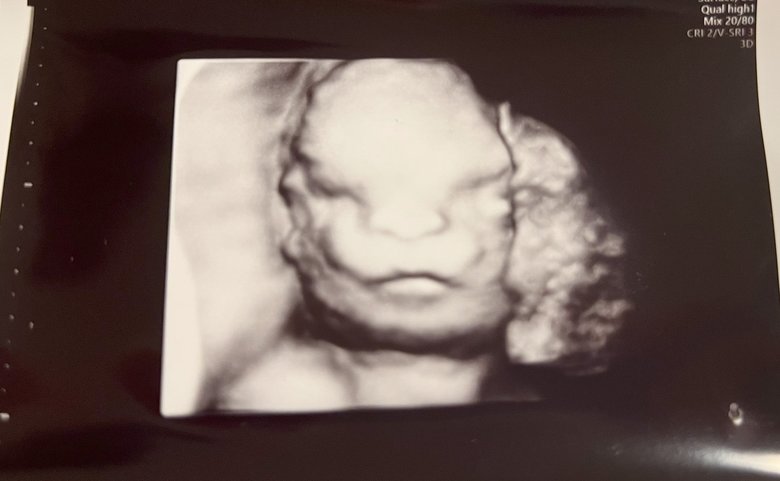

異常発覚後、妊娠24週(妊娠7か月)のころのエコー画像

7/28